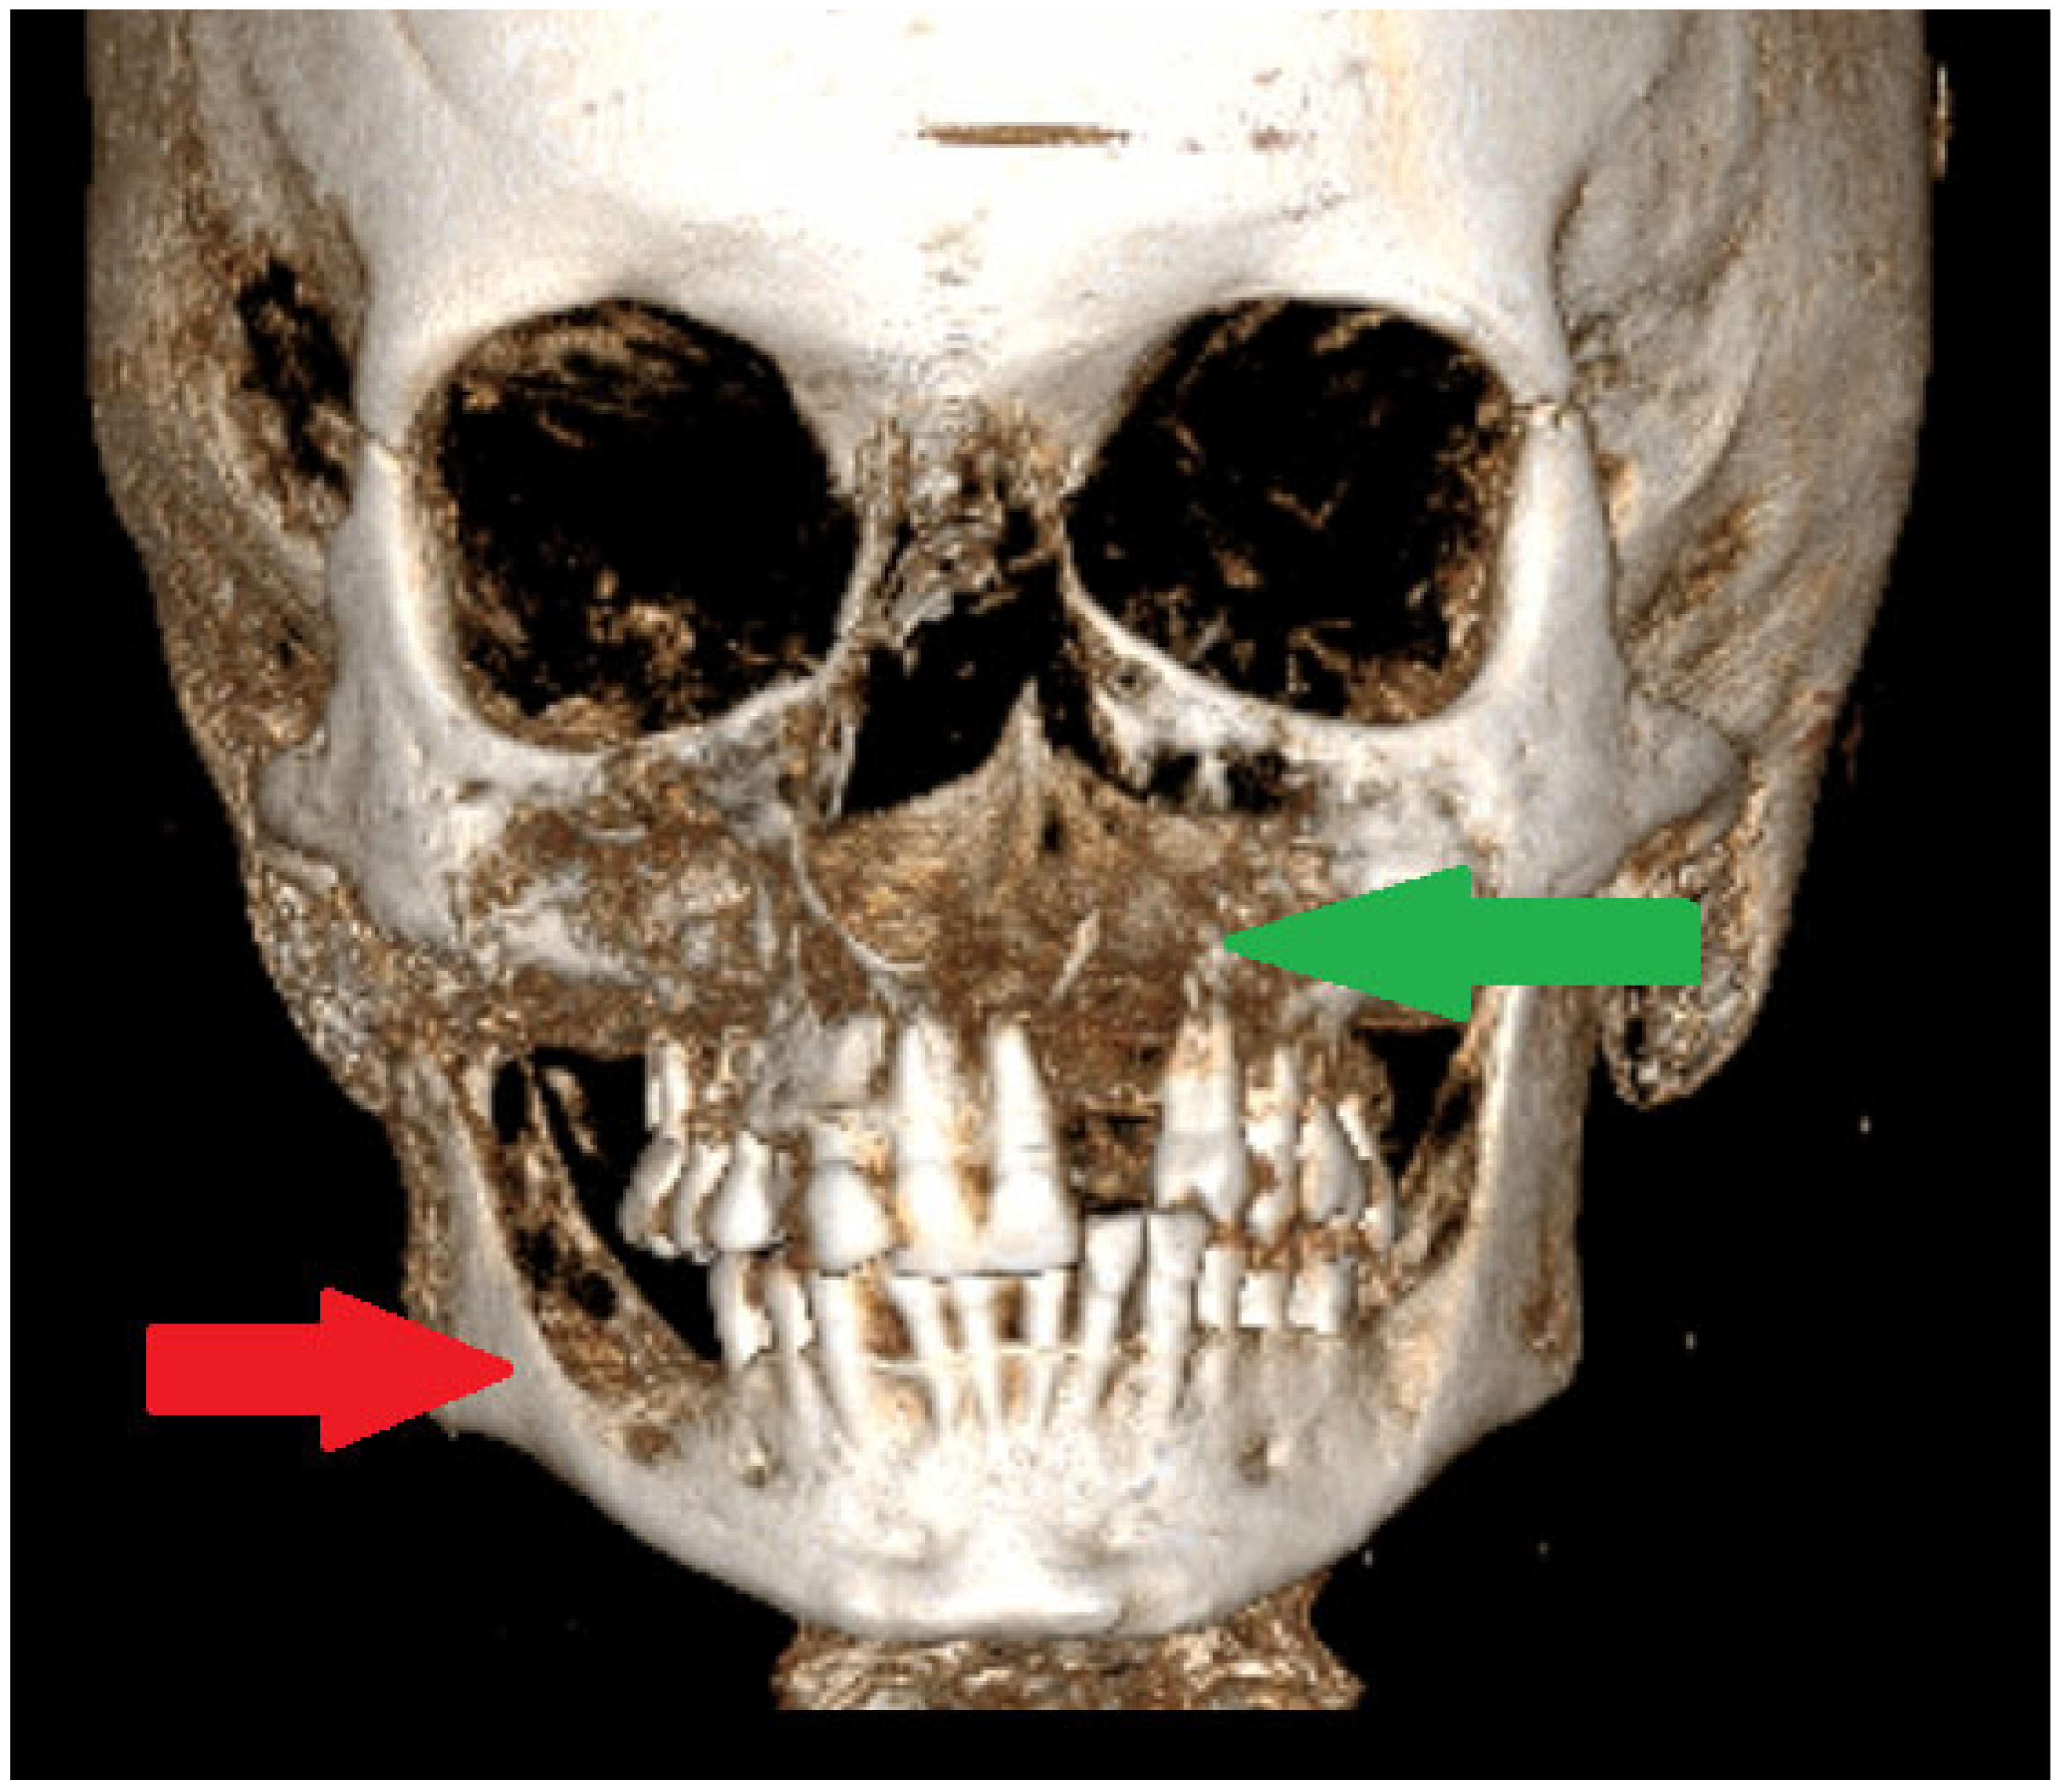

Figure 2. A CBCT-3D of jaw bones can greatly influence the scope of each surgical approach. Smaller bone lesions could be scheduled for a biopsy under local anesthesia. When, additionally, on facial skin, there are discoloured patches suggesting an early BCC (basal cell carcinoma), it is advisable to take two biopsies at the same time to improve the diagnosis of GGS. It is important to remember that GGS can be confirmed based on radiological and pathological evaluation and detailed clinical analysis. The following minor and major criteria for GGS confirmation were established [1,2,3]. The major criteria for NBCCS were as follows: two or more BCCs (basal-cell carcinomas) or one BCC before 20 years, the presence of two or more OKCs (odontogenic keratocysts), at least >3 cutaneous palmar or plantar pits, a 1st degree relative with NBCC (Nevoid basal cell carcinoma syndrome), and the presence of a medulloblastoma. On the other hand, the minor criteria for NBCCS were as follows: the presence of macrocephaly following the height adjustment; the presence of congenital orofacial defects such as frontal bossing, cleft palate, and hypertelorism; the presence of skeletal abnormalities such as syndactyly, pectus deformity or scapula defects, also the occurrence of a radiological abnormality such as fusion of the vertebras; hemivertebras; the bridging of Sella turcica and morphological defects of the hands and feet; the presence of an ovarian fibroma; and signs of bifid or fused ribs [1,2,3]. In many cases, during oral cavity, head, and neck evaluations, it is quite easy to see multiple cystic bone lesions, the presence of facial skin lesions/BCC, the presence of palatal defects and anomalies, and frontal bossing. In CBCT, it is easy to see a calcified falx cerebri and some disturbances with a high palate. The scope of each lesion might have different manifestations. In jaw surgery, special attention should be focused on extensive, expansile bone lesions causing visible bone disfigurement and bone asymmetry, and rarely occurring in the mandibular condyle head and temporomandibular area (TMJ). When TMJ structures are affected and the destruction of the joint occurs, some accompanying syndromes like joint pain, the inability to open the mouth, LMO-limited mouth opening, swelling and inflammation near the TMJ area, and problems with biting and chewing (red arrow). In elderly patients, this might also cause other problems related to prosthesis usage, overloading of the opposite side healthy joint, the growth of severe pain levels, and inflammation-related changes in the TMJ, which is where the OKC might spread [4,5]. Secondly, the problem is quite serious when a unicystic lesion of OKC has a polycystic appearance without borders and an expansive character causing bone asymmetry and cortical thickening, especially when present in the maxillary sinus, anterior maxillary bone, and alveolar process of the maxillary bone, or if any spread towards the nasal cavity (green arrow). Many approaches can be used to reduce the scope of resection, but the authors promote bone estectomy and allograft bone usage to strengthen the bones.